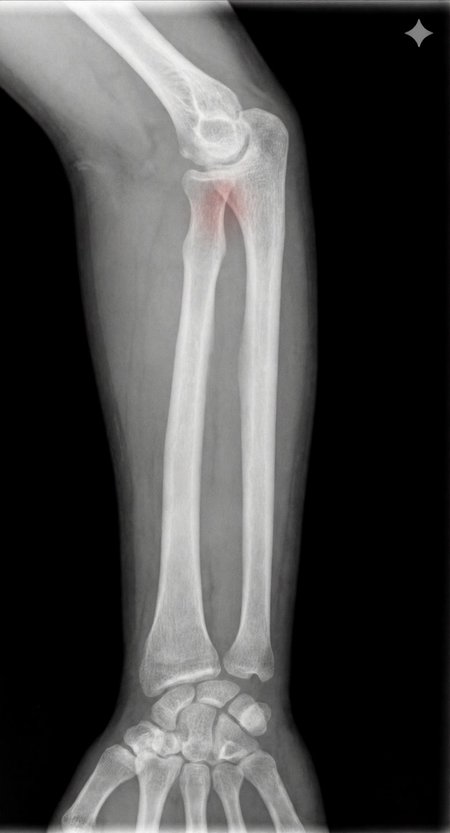

Can a model like Flux Kontext, designed for editing art and photography, be used to work with medical images, for example, with something 'as simple' as red-marking fractures?

The quick answer: it does do something interesting, but it over-scores and is far from reliable as a medical tool. It's a prototype to play with the idea, nothing more.

With a synthetic mini-dataset for Civitai of images made with 100% AI (10 healthy X-rays and 10 fractured):

False positives: 100% in healthy bones.

Fracture detection: ≈ 45%

Good for

AI prototypes and tests on medical imaging.

Eye-catching visualizations of "suspicious" areas in X-rays (experimental and creative art, here's an exotic tool xD)

Didactic/experimental material to play with sensitivity vs false positives.